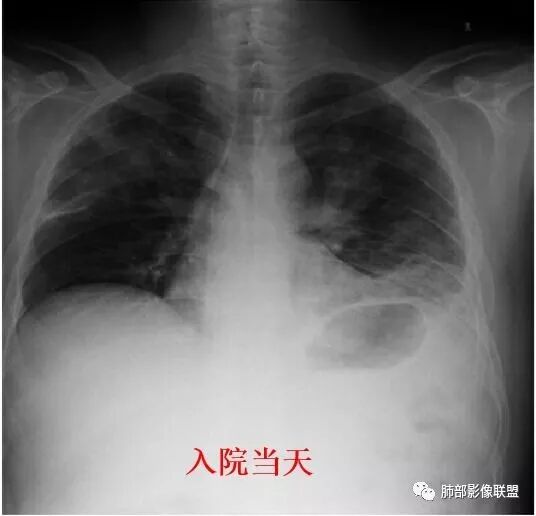

南边:患者男,44岁,以“发热1周伴咳嗽、咳痰3天” 入院。现 病 史:患者入院前1周无诱因出现寒战、发热,体温最高410C,伴肌肉酸痛、恶心、呕吐,就诊于我院, 血常规示白细胞及中性分类增高,予头孢呋辛静点1天,并口服抗生素等药物治疗。患者仍有发热,入院前3天出现咳嗽、咳暗红色血痰,伴左侧胸痛,咳嗽时加重,查胸片后收入我科。初学者:就是脓肿的话,也是坏死。然后肉芽肿边缘的壁;早期的话,它不会形成那种中央坏死壁强化的这种典型表现,但是它的特点是它很快会变化,所以有的时候不是很确定的时候,可以看那个随访。有没有高热,一般会这样判断是不是囊肿。但这个人因为肺部本身有病变,所以说,肝内的这个病变就没有办法鉴别了,那可以看一下他随访有没有变化,这个可以判断囊肿,就是从CT上它的这个壁,有的时候不是很好看,尤其是他脓肿,它形成的话,它有几个期。期不一样,它的壁的厚度、中间的坏死都不一样,所以有的时候它并不是特别的均匀,一般囊肿的话呢,我们会觉得它的分界跟周围的分解和非常的清楚,因为囊肿它是真壁。

南边:发热一周,高热糖尿病病史好像支持肺克雷伯杆菌感染

南边:胸膜下,类圆形,边界清,内有坏死,典型的反晕征,支气管壁增厚不明显,支持血道来源脓毒栓子所致梗死、感染

血培养:肺炎克雷伯 杆菌1次痰培养:肺炎克雷伯杆菌3次

治疗后改变